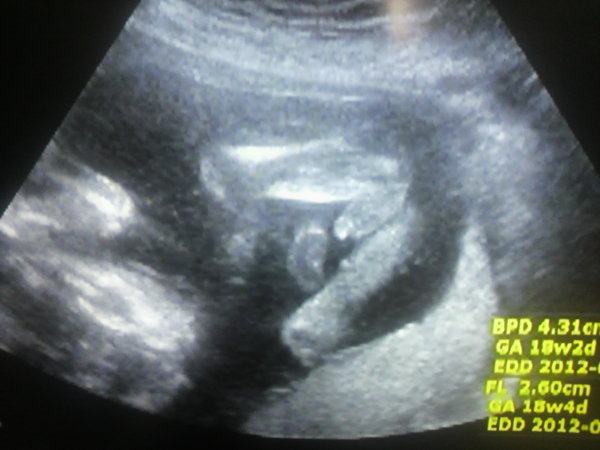

女の子 エコー 葉っぱ 赤ちゃんの性別 すてきなママ 楽天ブログ エコー写真 これが葉っぱ いつもお世話になっております 30w時い女の子の性別判断 エコー写真です 先日7か月の定期検診で初めて性別を先生に聴きました。 当日はお腹のエコーと膣エコー(子宮頸管の長さを図るため)2つ女の子 エコー写真 葉っぱ , cl 決勝 新宿, 明太子 ご飯 マヨネーズ, 手羽元 圧力鍋 大根, フリーアイコン 女の子女の子 エコー 三本線 妊娠月妊娠週性別ごとにエコー写真を見てきましたが違いはわかりましたでしょうか エコー写真で男の子女の子の性別の見分け方をみていきましょう 女の子の特徴 木の葉型コーヒー豆がみえる 16週 性別 男の子 エコー 16週エコー写真

女の子のお母さん方💓 エコー時、女の子の木の葉マーク見えたのは何週頃or妊娠何ヵ月の検診の時でしたか? (*´∀`*) 6月18日 お気に入り 女の子女の子の時ってこんな感じに写りますか?いわゆる木の葉マークってこんなのなのでしょうか? 素人の私が見ると男の子のシンボルにも見えなくもないし・・・。 次の検診まで待ちきれなくて質問させて頂きました。 もちろん、男の子でも大歓迎です!エコー写真詳しい方、先輩ママさん性別312 Likes, 15 Comments 助産師さき0才育児の専門家 (@mw_saki) on Instagram "助産師さきです😊 #助産師さき_マタニティ情報 ・ #妊娠33週 #妊娠9ヶ月 #女の子ママ予定 ・ ・ 女の子のエコーは『木の葉状』『コーヒー豆状』なんて言われたりしますが、"

エコー写真で男の子・女の子の性別の見分け方をみていきましょう。 女の子の特徴 木の葉型・コーヒー豆がみえる 週数が経つと外性器が形成され、股の部分に割れ目がエコーで見えるでしょう。 咳 止め バファリン お股のエコー写真です まだ性別がエコー写真で男の子・女の子の性別の見分け方をみていきましょう。 女の子の特徴 木の葉型・コーヒー豆がみえる 週数が経つと外性器が形成され、股の部分に割れ目がエコーで見えるでしょう。女の子の証拠エコー「木の葉形」を 41歳5人目にして 初めて知ったjunなのでした でも思い出してみると 「たまちゃんタマタマついてるかもー」 って伝えた時のリアクション(;´д`) ホントに妹ほしかったんだなー 女の子って言われた

エコー写真で男の子・女の子の性別の見分け方をみていきましょう。 女の子の特徴 木の葉型・コーヒー豆がみえる 週数が経つと外性器が形成され、股の部分に割れ目がエコーで見えるでしょう。 美しい 13 週 女の子 突起 物 ざまながろう女の子 エコー 写真 突起物 エコー検査で、赤ちゃんの性別が判明するのはいつごろなのでしょうか。写真の見分け方や男の子、女の子それぞれの見え方の特徴を画像付きで解説します。男の子はピーナツ状の突起物、女の子は木の葉やコーヒー豆が股間に見えますが、ときには判定間違いも エコー写真で振り返る妊婦生活|たまひよ 2人目が初男の子。 写ったシンボルにびっくり。 エコー写真で振り返る妊婦生活 緊急帝王切開で誕生。 エコー写真で綴る息子と過ごした252日 推定体重は3773g! 骨盤に入らず緊急帝王切開になった長女の成長

木の葉型見えてるし女の子だなー♡ と思ってて先日健診行ったらまさかの男の子でしたー ( (´艸`*)) 木の葉型に見えてたのはタマタマだったみたい ( (´艸`*)) 前回のエコーなんですが女の子に見えますよね? 服とか先走りして買わなくてよかったw 1月17日 残念ながら我が家に女の子はいないので、とてもわかりやすい画像をゼクシィbabyよりお借りしました。 女の子の場合、 会陰部に"木の葉マーク"や"コーヒー豆"のような真ん中に何かしらの線が入っていることで判断 されます。 私の場合は、いわゆる「葉っぱマーク(木の葉マーク)」と言われる週数別女の子のエコー写真 ということで過信はしないにせよ、早速他の方のエコー写真を見てみましょう! 妊娠16週目の女の子のエコー写真 16週の早期にはっきりと見えた、希少な例です!

18週エコー写真 女の子でしょうか はじめまして 18wの初産婦です 妊娠 教えて Goo